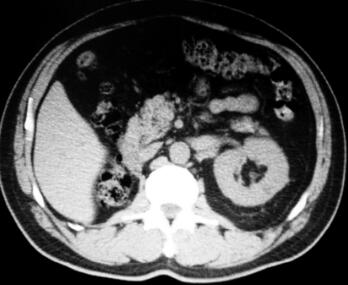

2.全腹CT(2011年12月28日):左肾可见一类圆形低密度影,直径约0.8cm,其内CT值为15HU,扫描范围内右肾未见显示,其他肝脏、脾脏、胆囊、胰腺、膀胱、前列腺均正常,腹膜后及盆腔未见增大淋巴结。诊断建议:左肾小囊肿,右肾缺如,术后改变(图2)。

图2